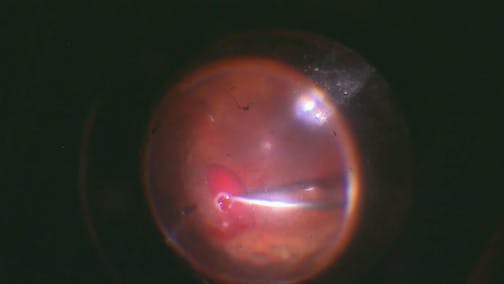

Optic Nerve Pit

Kourous A. Rezaei, MD